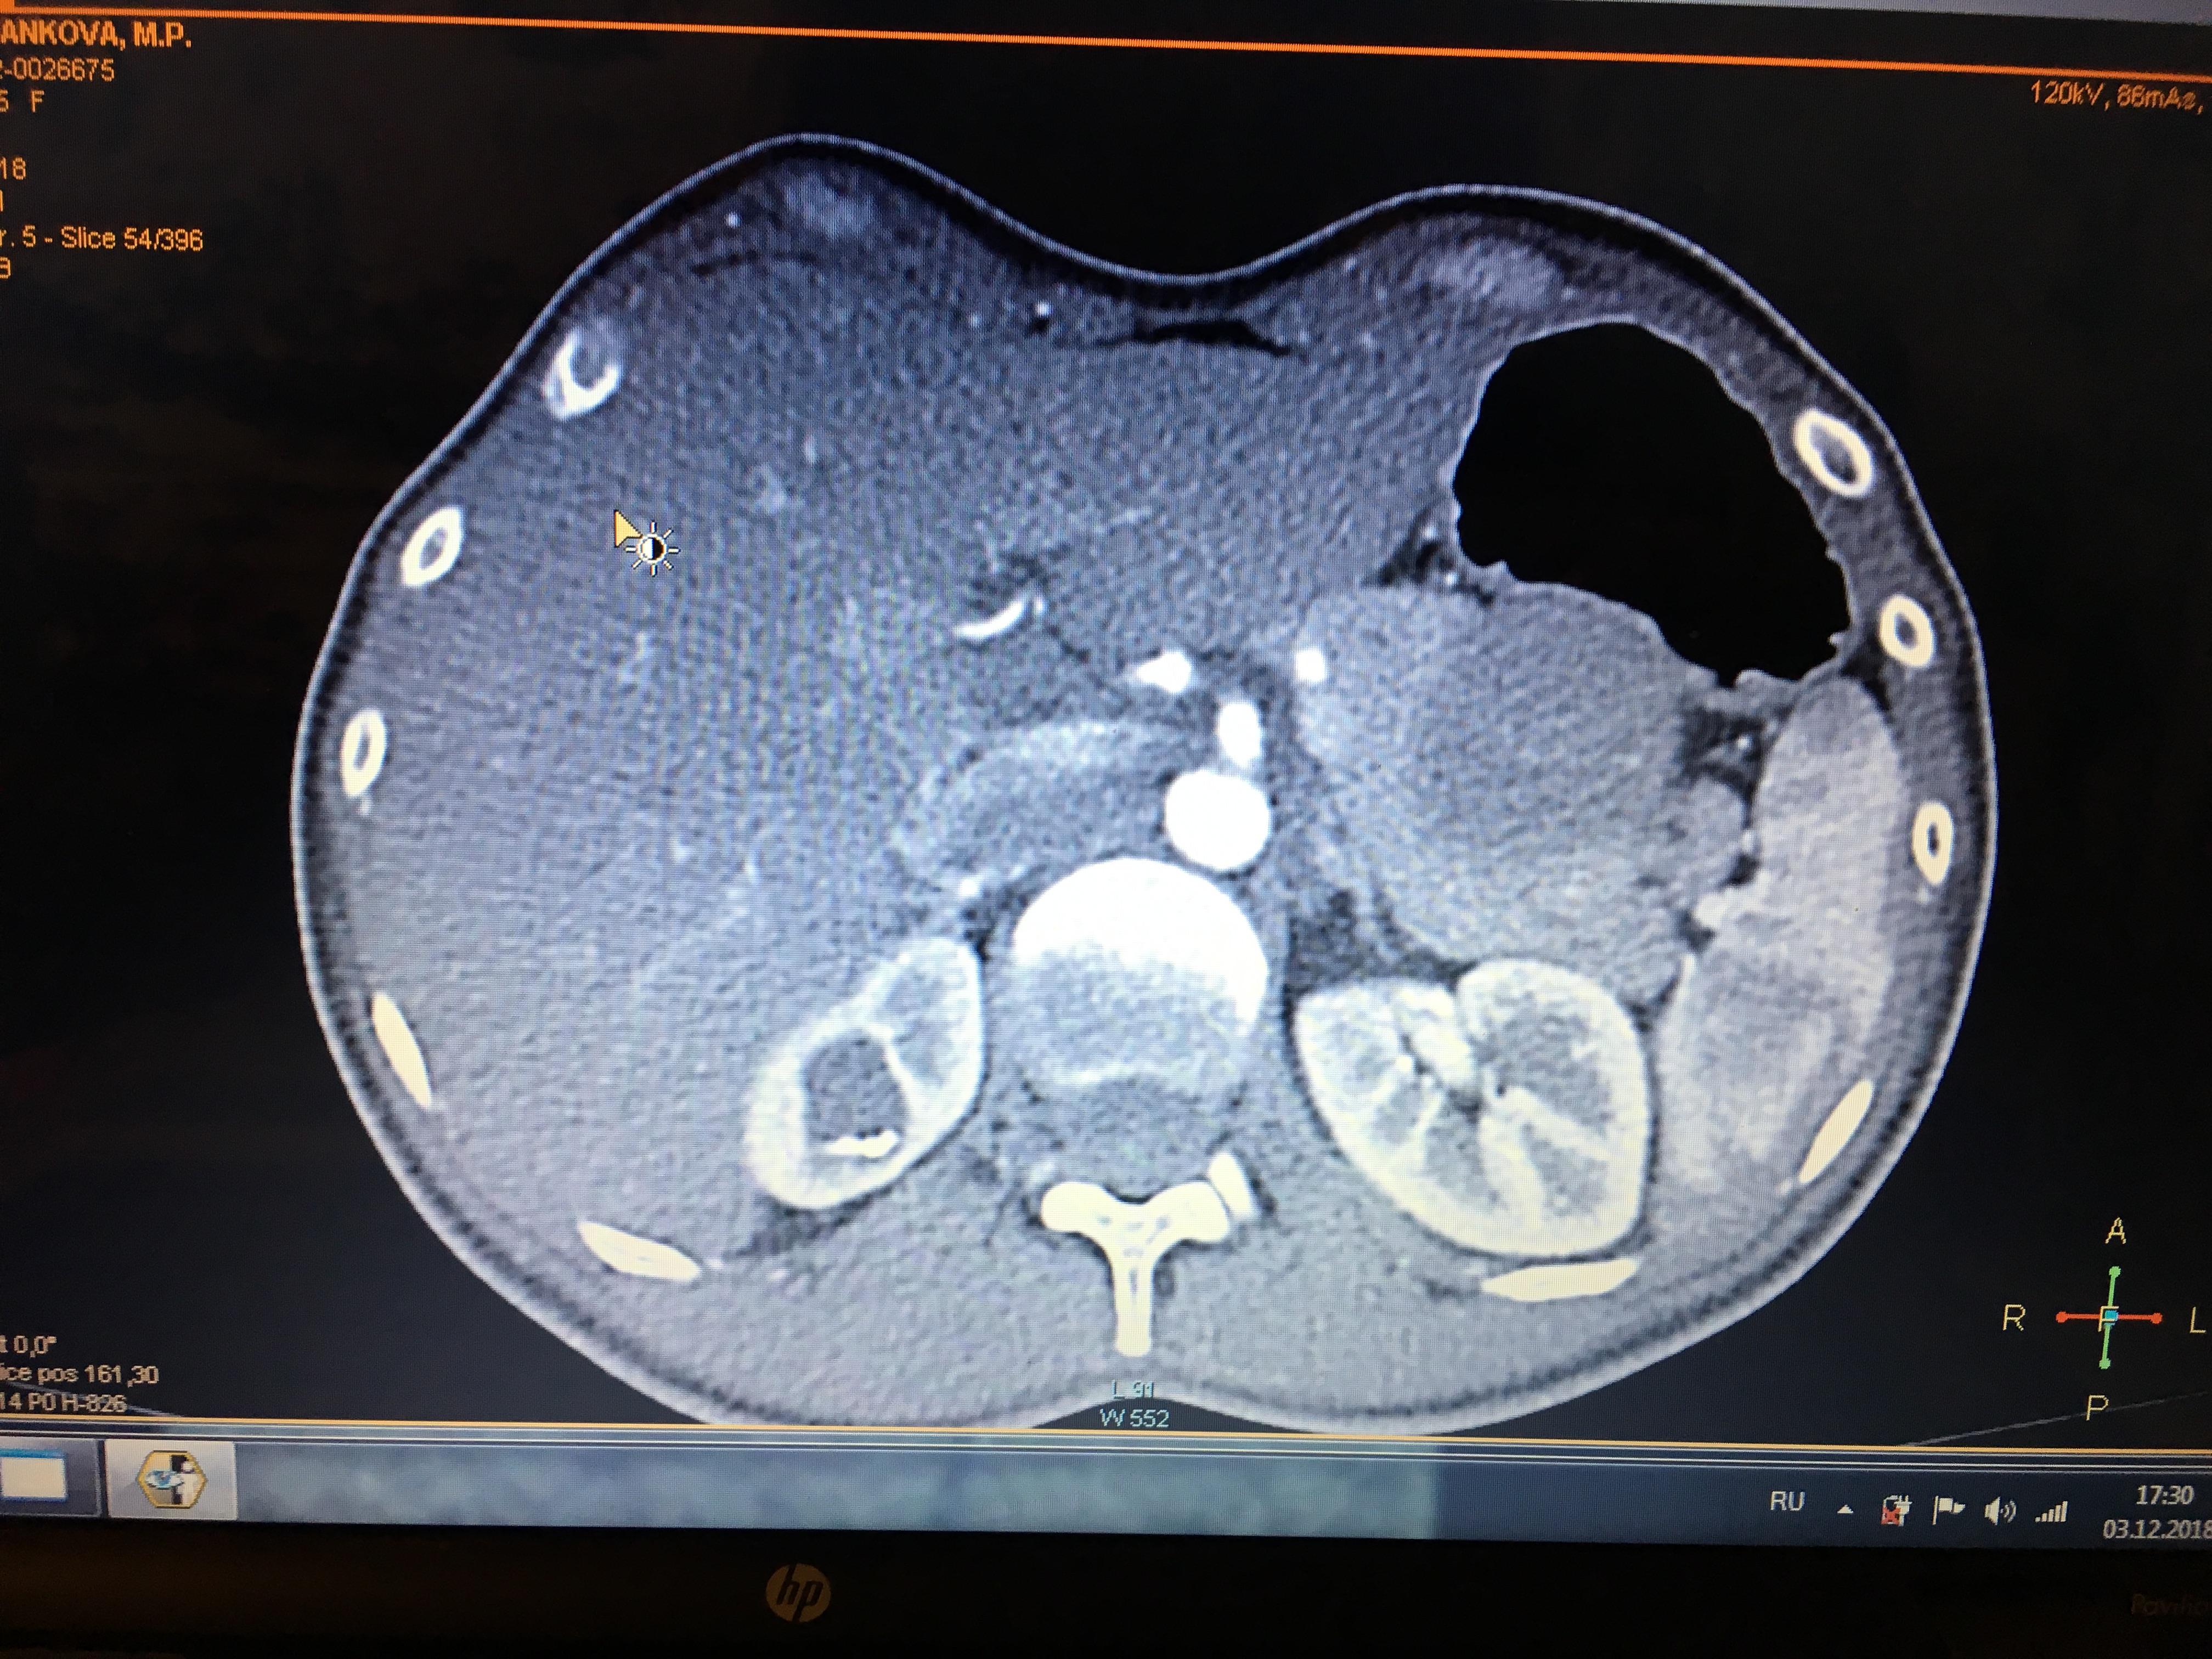

Здравствуйте,помогите, пожалуйста, с расшифровкой кт почек с контрастом. Насколько я поняла, в левой почке маленький камешек. А что за образование в правой почке? Киста с кальцинированной стенкой или камень? Спасибо за ответ!

Здравствуйте! На последнем снимке - больше данных за конкремент. Но при описании снимков должны определяться плотность образования, и нет изображения ни одного фрагмента ни одного из мочеточников. И самих снимков обычно бывает больше. Недостаточно данных для заключения.